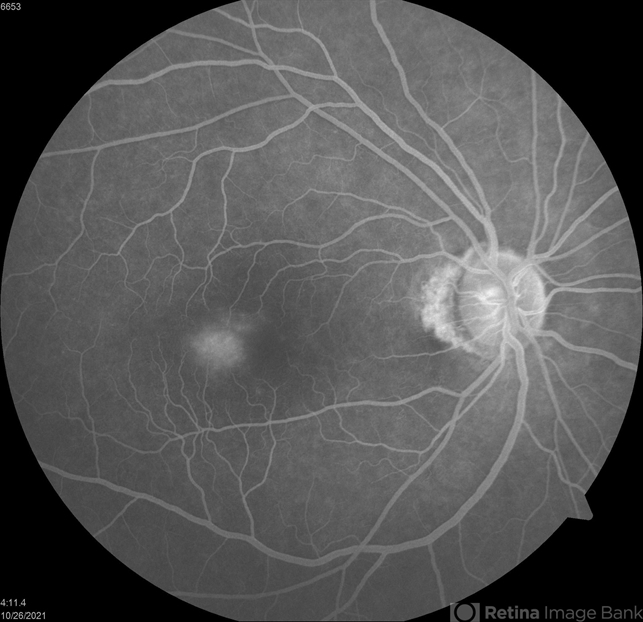

- Macular Telangiectasias

- juxtafoveal telangiectasis, idiopathic macular telangiectasia, parafoveal telangiectasia

- Fluorescein angiogram of a 56 y.o. M with parafoveal telangiectasias. Early transit images show the delicate abnormal capillary network in the temporal parafoveal region. Late transit images show mild leakage.